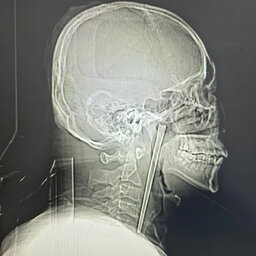

A Man In China Lived With A Long Metal Chopstick Stuck In His Throat For EIGHT YEARS